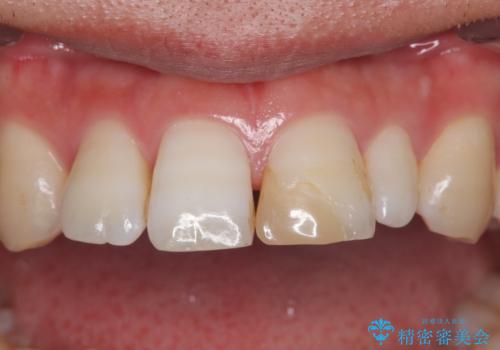

つぎはぎだらけの前歯を周囲と調和させたい オールセラミッククラウン補綴治療

- 隙間を埋めた材料の変色や形を気にして来院された患者様です。

矯正治療などを含めて治療方法を相談した結果、当該歯をオールセラミッククラウンにて補綴治療を行うこととしました。

前歯の単独歯の補綴治療であったので、オーダーメイドタイプをおすすめしましたが、今回は既製タイプにて製作を進めました。

既製タイプでしたが、違和感のない仕上がりとなりました。